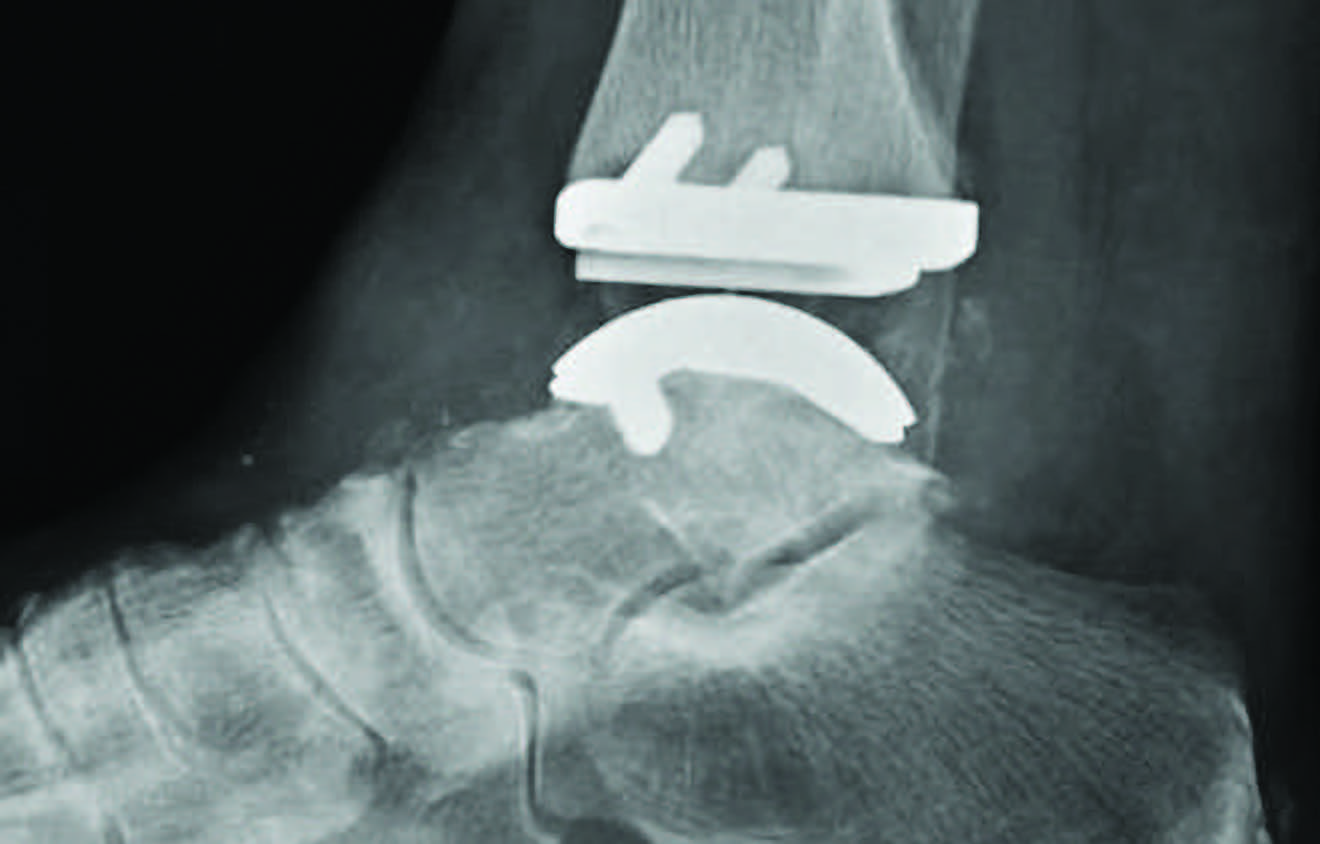

The “appropriate” statements address concepts related to determination of causes and types of ankle arthritis; assessment of instability and alignment; appropriate use of X-rays and advanced imaging; multimodal pharmacology; bracing; intra-articular corticosteroids; realignment osteotomy; open and arthroscopic arthrodesis; total ankle arthroplasty; and amputation. The “neither appropriate nor inappropriate” statements discuss the topics of physical therapy, cast immobilization, nonsteroidal intra-articular injections, articular resurfacing, arthroscopic debridement and arthrodiastasis.

Not unexpectedly, definitive surgical management by arthrodesis through open or arthroscopic technique and total ankle arthroplasty did achieve consensus as viable options, points out Dr. Theodoulou.

“Early management should be conservative with bracing and judicious use of isolated glucocorticoid injection if not contraindicated. With advanced pain and dysfunction, it is appropriate to offer definitive surgical management by arthrodesis or total ankle arthroplasty considering the individual patient requirements and health status,” maintains Dr. Theodoulou.